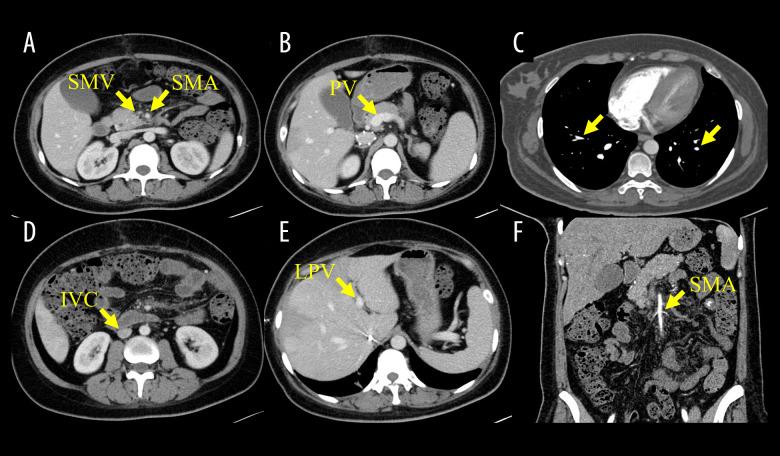

BACKGROUND Women are at an increased risk of developing venous thrombosis during gestation and the postpartum period, due to physiological and anatomical changes. Superior mesenteric vein thrombosis (SMVT) is a rare and severe complication with a dangerous course and a high mortality rate. Heparin-induced thrombocytopenia (HIT) is also rare in patients treated with heparin and presents with thrombosis and thrombocytopenia. We report a patient with SMVT diagnosis who was treated with heparin anticoagulation after surgery and eventually developed HIT. CASE REPORT The patient was a 30-year-old woman with a diagnosis of SMVT 10 days after giving birth to her second child. She was treated with heparin anticoagulation and interventional catheter-based thrombolysis and thrombectomy, which was ineffective, and she showed peritonitis. We therefore performed an emergency laparotomy, during which we found partial small intestine necrosis and performed a partial small bowel resection. However, the systemic thrombosis worsened postoperatively, and after a multidisciplinary team consultation, HIT was diagnosed. After switching to non-heparin anticoagulation, the patient's condition improved, and she was discharged from the hospital. CONCLUSIONS This is the first case report of HIT secondary to heparin anticoagulation in a parturient who underwent surgery for intestinal necrosis caused by SMVT. Our case highlights the challenge of treating SMVT and the difficulty of diagnosis of HIT. SMVT is a serious condition that requires sufficient experience to judge the timing of surgery. HIT is a rare complication that occurs during heparin use, and its timely diagnosis and treatment have a significant impact on patient prognosis.

由于生理和解剖学变化,女性在妊娠期和产后发生静脉血栓形成的风险增加。肠系膜上静脉血栓形成(SMVT)是一种罕见且严重的并发症,病程凶险,死亡率高。肝素诱导的血小板减少症(HIT)在接受肝素治疗的患者中也很罕见,表现为血栓形成和血小板减少。我们报告一例诊断为SMVT的患者,术后接受肝素抗凝治疗,最终发生了HIT。病例报告:该患者为一名30岁女性,在生下第二个孩子10天后被诊断为SMVT。她接受了肝素抗凝以及基于介入导管的溶栓和血栓切除术,但治疗无效,且出现了腹膜炎。因此,我们进行了急诊剖腹手术,术中发现部分小肠坏死并进行了部分小肠切除术。然而,术后全身血栓形成恶化,经过多学科团队会诊,诊断为HIT。改用非肝素抗凝后,患者病情好转并出院。结论:这是首例关于因SMVT导致肠坏死而接受手术的产妇在肝素抗凝后发生HIT的病例报告。我们的病例突出了治疗SMVT的挑战以及HIT诊断的困难。SMVT是一种严重疾病,需要足够的经验来判断手术时机。HIT是肝素使用过程中发生的罕见并发症,其及时诊断和治疗对患者预后有重大影响。